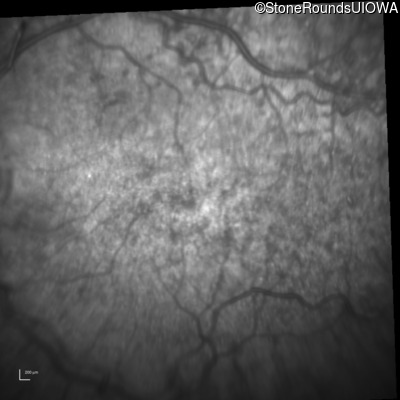

Infrared Fundus Photograph - Right - 20/200 +1

Exemplar